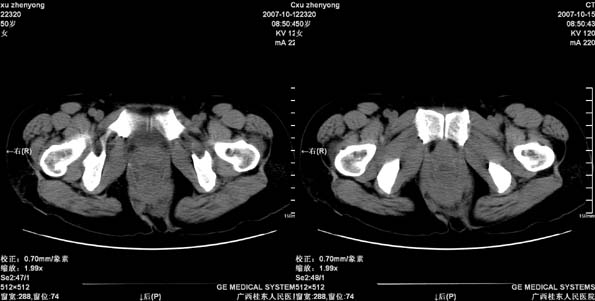

患者,女 50岁.会阴部坠胀感一月余,有痔疮病史,近期有便血;患者今年5月分结肠镜检查未见异常(由于患者不愿意ct增强扫描)没做增强,现准备手术,请各位老师会诊.

直肠壁明显增厚,呈块状表现,肠腔狭窄闭塞,考虑ca

直肠壁增厚明显,周围脂肪间隙模糊,见有小淋巴结显示,前方与阴道后壁分解不清。考虑直肠癌可能性大

不做强化,但平扫保留灌肠一定要做好。现在看直肠壁增厚明显,周围脂肪间隙模糊,前方与阴道后壁分界不清。考虑直肠癌可能性大